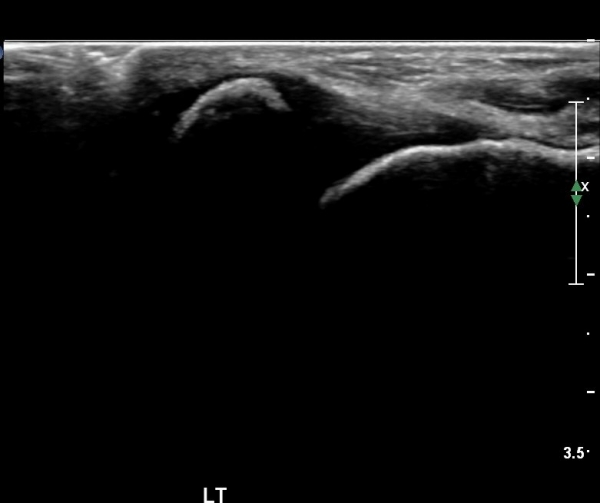

Àü°ÅºñÀÎ´ë ºÎÀ§ ±¹¼ÒÀû ¾ÐÅë, ºÎÁ¾À» º¸ÀÓ. Àü¹æ´ç±è°Ë»ç (+)

ÃÊÀ½ÆÄ °Ë»ç